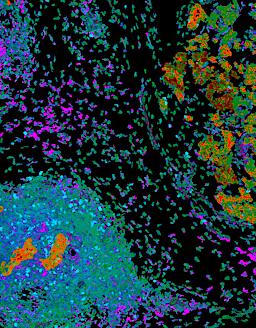

Pancreatic ductal adenocarcinoma is a lethal disease with limited treatment options and poor survival. We studied 83 spatial samples from 31 patients (11 treatment-naïve and 20 treated) using single-cell/nucleus RNA sequencing, bulk-proteogenomics, spatial transcriptomics and cellular imaging. Subpopulations of tumor cells exhibited signatures of proliferation, KRAS signaling, cell stress and epithelial-to-mesenchymal transition. Mapping mutations and copy number events distinguished tumor populations from normal and transitional cells, including acinar-to-ductal metaplasia and pancreatic intraepithelial neoplasia. Pathology-assisted deconvolution of spatial transcriptomic data identified tumor and transitional subpopulations with distinct histological features. We showed coordinated expression of TIGIT in exhausted and regulatory T cells and Nectin in tumor cells. Chemo-resistant samples contain a threefold enrichment of inflammatory cancer-associated fibroblasts that upregulate metallothioneins. Our study reveals a deeper understanding of the intricate substructure of pancreatic ductal adenocarcinoma tumors that could help improve therapy for patients with this disease.